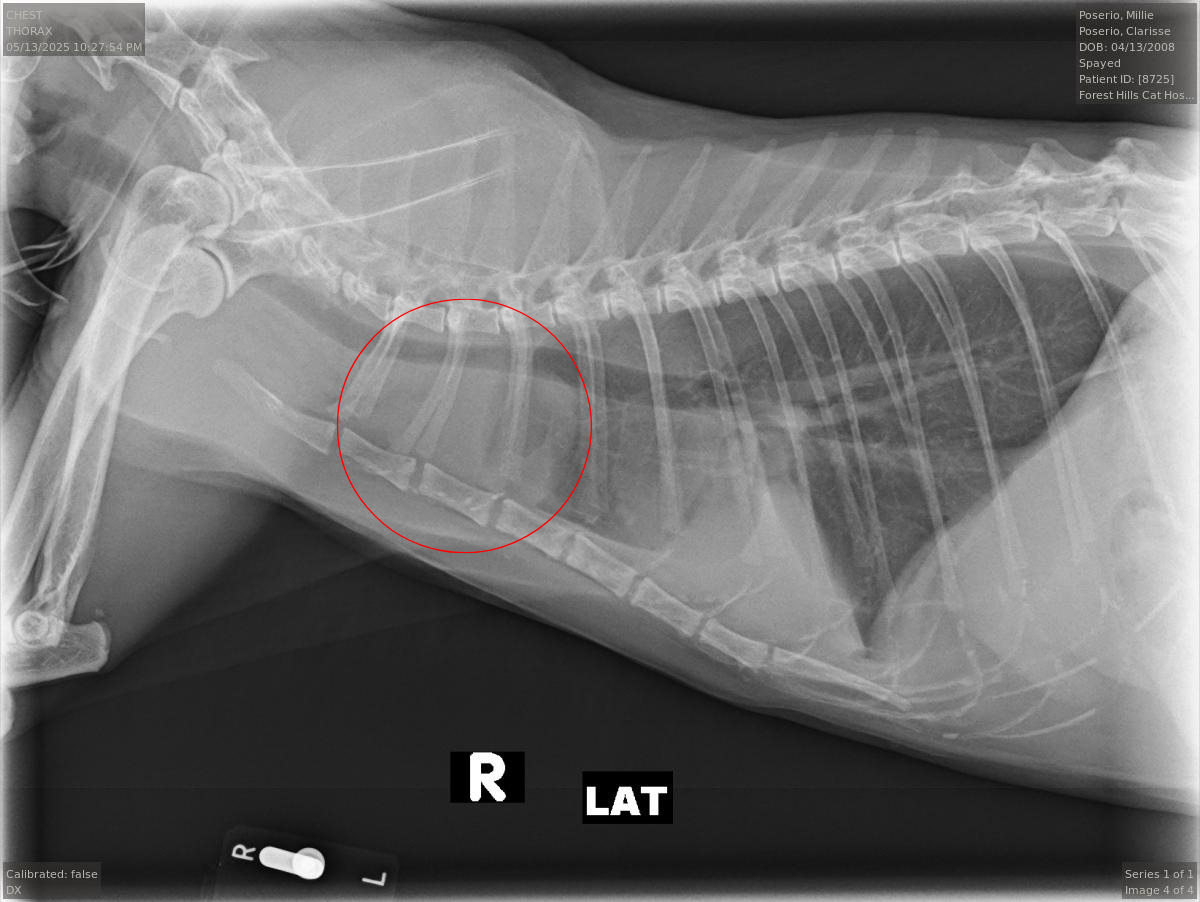

Millie has always been a fighter. She beat hyperthyroidism, has been managing chronic kidney disease, and lives with a heart murmur, but none of that has ever dimmed her spirit. Recently, at what should have been a regular checkup, X-rays revealed a mass in her chest and fluid around her lungs. We were referred immediately to the Animal Medical Center for further testing, and she was hospitalized there for close monitoring.

The mass has been confirmed to be a rare neuroendocrine tumor, but further testing is still needed. Our next step is for her to get a CT scan in order for the oncology team to figure out a treatment plan.